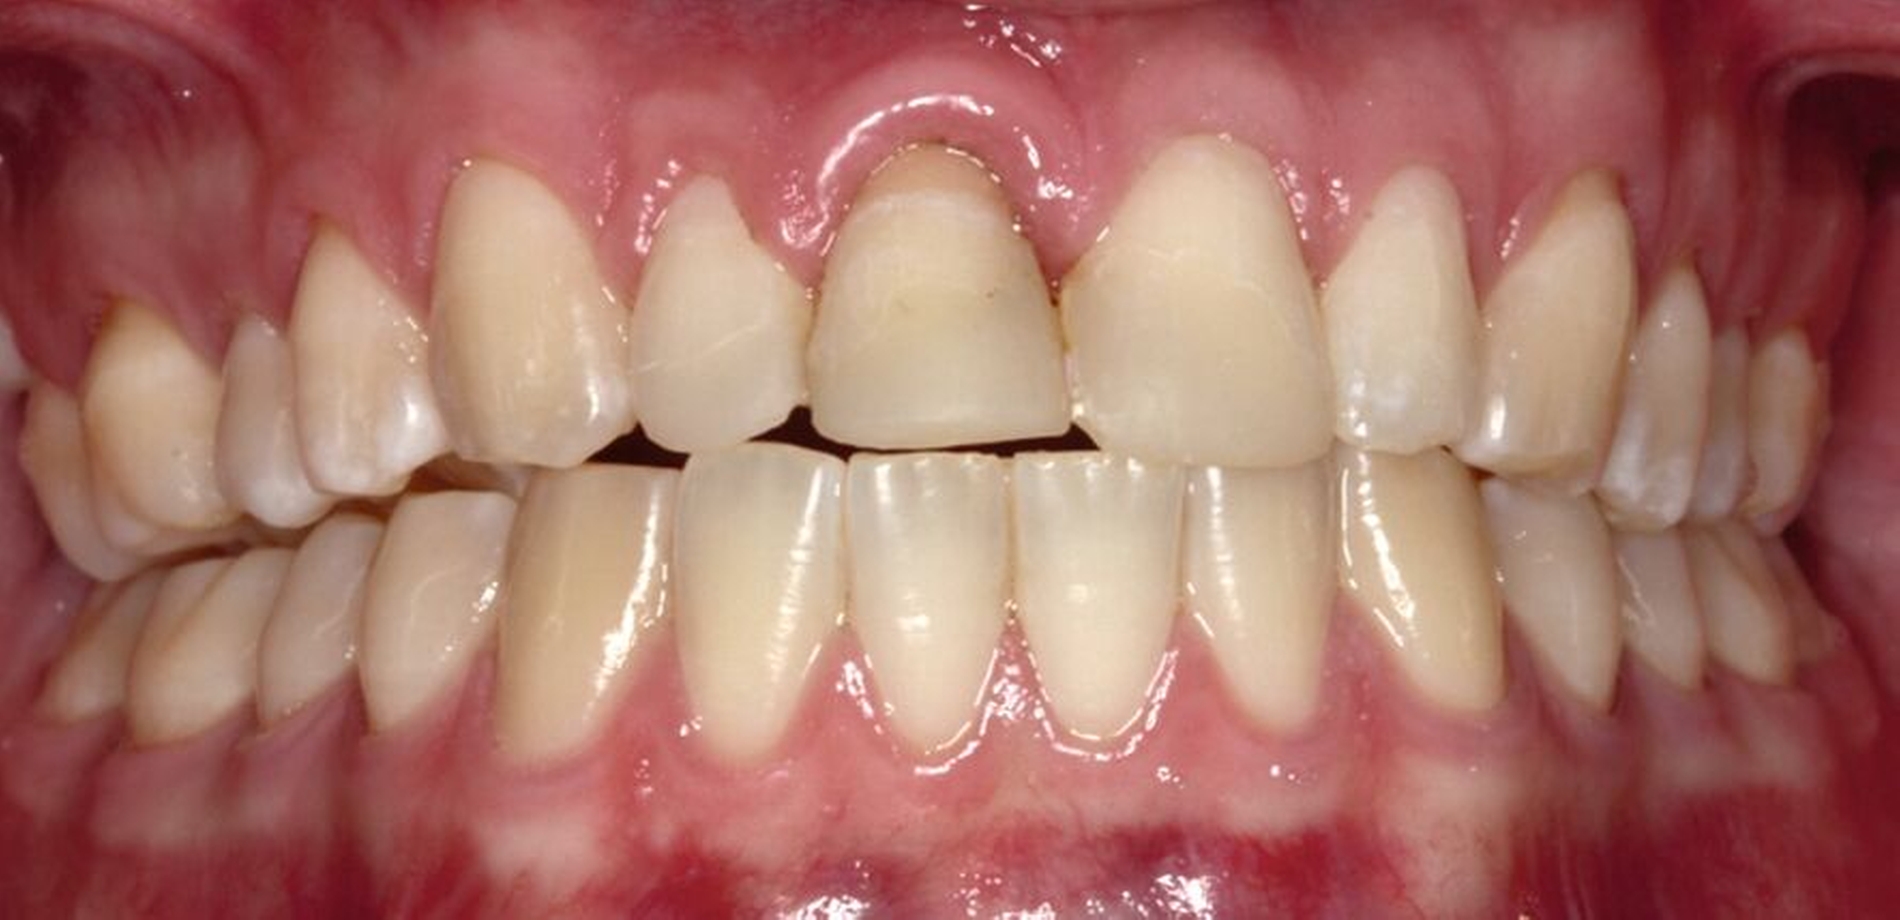

Ein 22-jähriger Patient stellte sich im Februar 2020 im zahnärztlichen Notdienst der Klinik für Zahn-, Mund- und Kieferkrankheiten Mainz vor. Aufgrund einer Synkope war er mit dem Oberkiefer auf den Rand einer Badewanne gestürzt. Intraoral zeigte sich der Zahn 12 mit einer Schmelz-Dentin-Fraktur ohne Pulpabeteiligung (unkomplizierte Kronenfraktur), der Zahn 11 mit einer Kronen-Wurzel-Fraktur mit Pulpabeteiligung und der Zahn 21 mit einer Schmelz-Dentin-Fraktur mit Pulpabeteiligung (komplizierte Kronenfraktur). Die Zähne zeigten keine erhöhten Lockerungsgrade oder Dislokationen (Abbildung 2). Herausfordernd für die weitere Versorgung war der Frakturverlauf an Zahn 11, an dem die Frakturkante palatinal tief subgingival und mesio-palatinal auch subkrestal lag. Röntgenologisch konnte die klinisch gestellte Verdachtsdiagnose bestätigt und eine Wurzelfraktur ausgeschlossen werden (Abbildung 3).